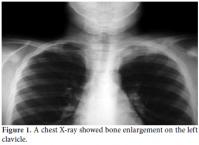

A 10-year-old boy was referred to the Pediatric Rheumatology Unit at the University Hospital Federal University of Pernambuco, Recife in 2008 with a fiveyear history of intermittent pain in his left clavicle, right hip, ankles, and dorsal spine. In 2006, he was admitted to the Pediatric Unit complaining of back pain, fever, and a mass over his left clavicle. Blood tests showed a C-reactive protein (CRP) level of 24 mg/dl and an erythrocyte sedimentation rate (ESR) of 39 mm/h. A chest X-ray confirmed the mass over his left clavicle (Figure 1). Septic osteomyelitis was diagnosed, although his blood and bone cultures were negative. A course of an empirical antibiotic (cephalothin) and NSAIDs was prescribed. He was later referred (after one year) to the Orthopedic Unit where a thoracic computed tomography (CT) scan showed the volume of the left clavicle had increased due to an area of hyperostosis mixed with osteolysis. Hence, the antibiotic was changed to ciprofloxacin for three months. As there was no improvement, he was referred to the Pediatric Rheumatology Unit, where a tuberculin test and ANA were negative. A bone scan showed an increased technetium-99m (99mTc) radioisotope uptake at the left clavicle, ankle, sacroiliac joints, and T8 thoracic disc (Figure 2). Magnetic resonance imaging (MRI) demonstrated multiple inflammatory lesions between the T7 and T9 disks (Figure 3) and in the left clavicle and left ankle (Figure 4), thus confirming the findings on the bone scan and thorax CT. The results of the histological analysis of a bone biopsy were compatible with aseptic chronic osteomyelitis (Figure 5). No infection was identified by lesion or blood culture, and no malignancy was detected by imaging; hence, the possibility of CRMO was raised. An aggressive treatment with NSAIDs, alendronate 70 mg/week, methotrexate 15 mg/week, and infliximab 5 mg/kg was initiated due to the severity of the case and the delay in diagnosis. After the third infusion of infliximab, the boy became free of pain. His ESR and CRP levels were normal, and a bone scan showed a tiny uptake at the left clavicle. It should be noted that the patient and his family gave their consent for any treatment provided at the Pediatric Rheumatology Unit.